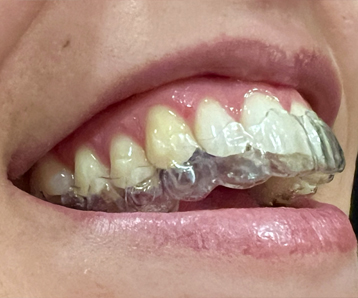

Los trastornos temporomandibulares son afecciones de los músculos faciales y/o de las articulaciones temporomandibulares (ATM). Estos problemas pueden provocar: dolor constante o intermitente en la cara, la cabeza o cerca del oído, dificultad para abrir la boca o sonidos al moverla.

La causa a menudo es difícil de determinar, pero se relaciona con factores como el estrés, el bruxismo (acción involuntaria de rechinar o apretar los dientes) o traumatismos.

El tratamiento más frecuente incluye cambios de hábitos, el uso de férulas oclusales y, en muchos casos, fisioterapia.